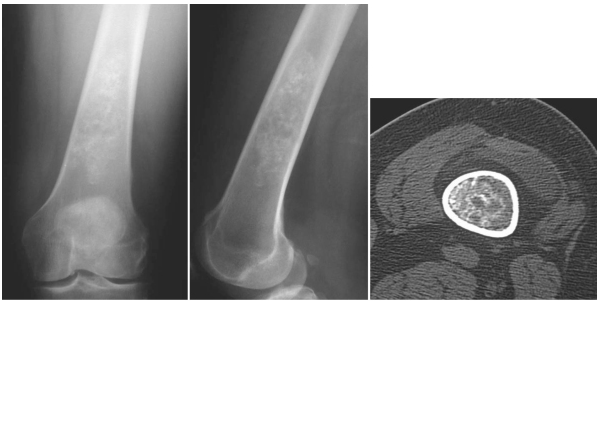

DEV HÜCRELİ TÜMÖR

Doktor Mehmet Subaşı

Sıklıkla 20-40 yaş arasında görülür, kadınlarda ise daha ...